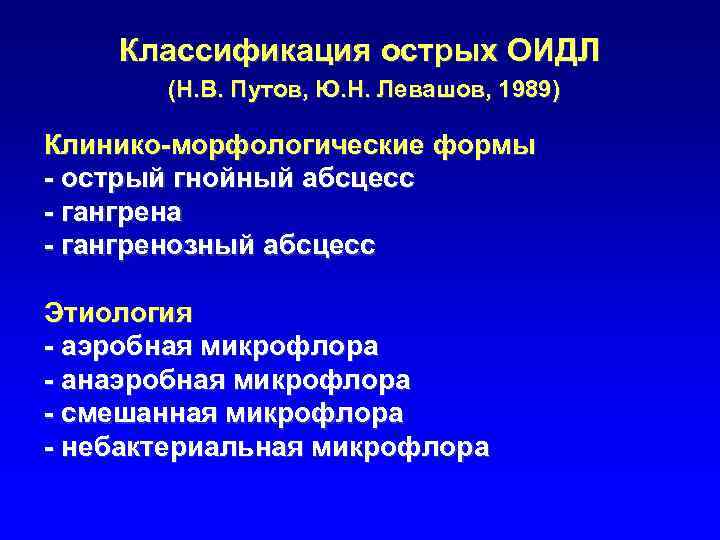

Классификация острых ОИДЛ (Н. В. Путов, Ю. Н. Левашов, 1989) Клинико-морфологические формы - острый гнойный абсцесс - гангрена - гангренозный абсцесс Этиология - аэробная микрофлора - анаэробная микрофлора - смешанная микрофлора - небактериальная микрофлора